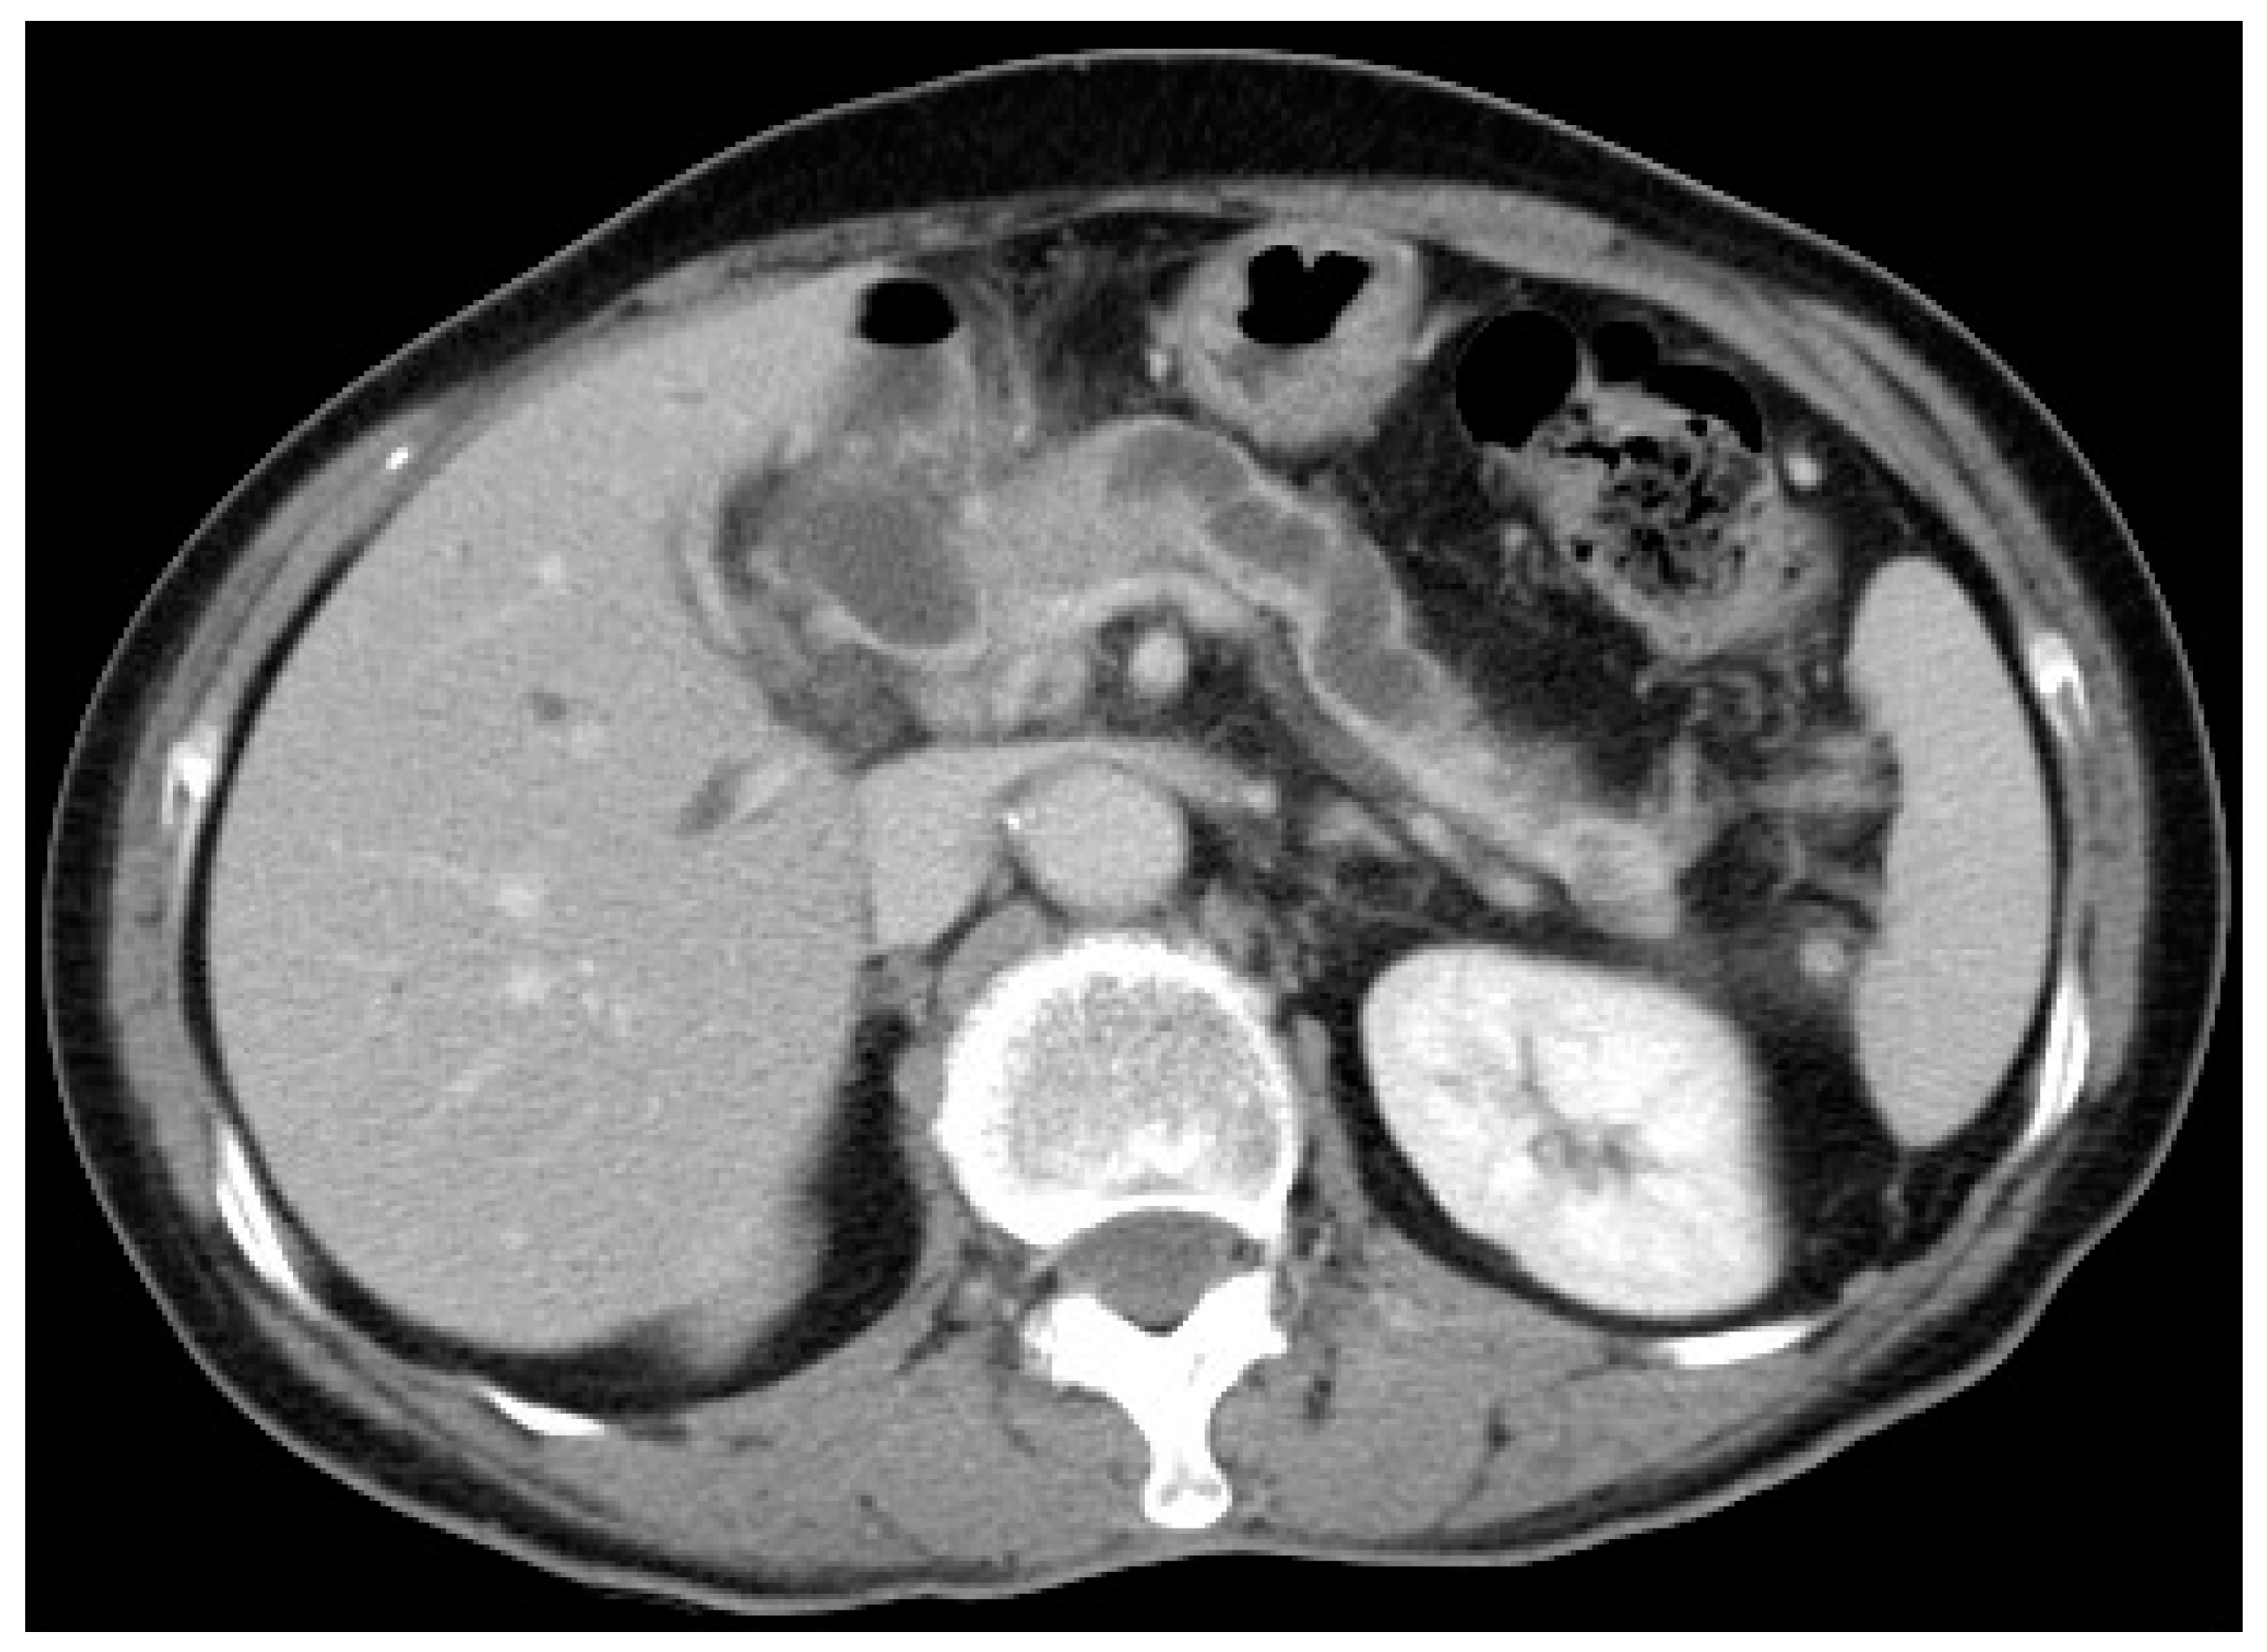

6.2. Endoscopic Ultrasound

7. Same-Session EUS and ERCP